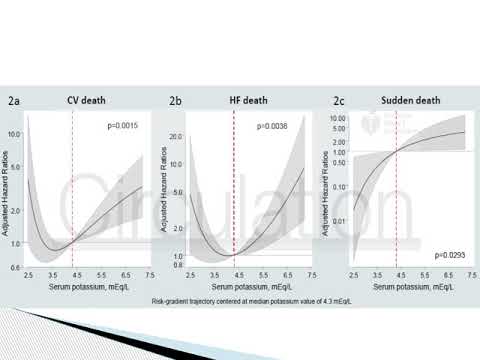

Monitoreo de potasio en insuficiencia cardíaca y riesgo de muerte. Dr. Mariano Napoli Llobera. Residencia de Cardiología. Hospital C. Argerich. Buenos Aires